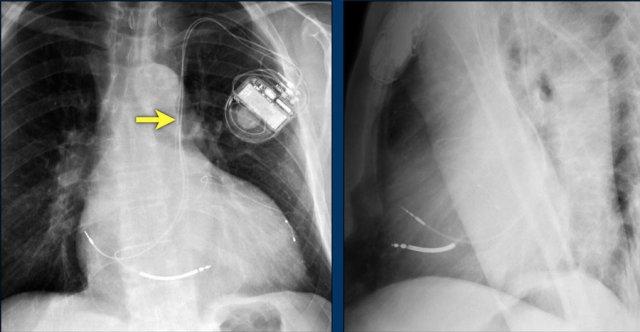

Bệnh nhân này đã được sửa chữa ba van:

- Van hai lá

- Van ba lá

- Van động mạch chủ

Có máy tạo nhịp tim với điện cực thượng tâm mạc.

Phương án này được lựa chọn vì người ta cho rằng điện cực đặt theo đường thông thường vào thất phải sẽ ảnh hưởng quá nhiều đến chức năng của van ba lá nhân tạo.

Mũi tên trắng chỉ vào van động mạch chủ.

Mũi tên vàng chỉ vào van hai lá.